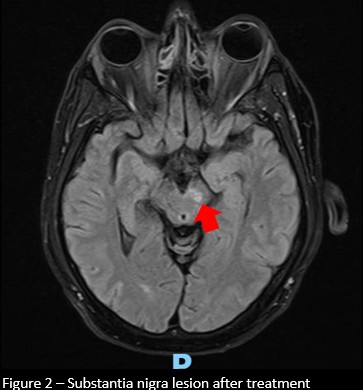

Results: A 58-year-old male patient was admitted for evaluation of one month of anterograde amnesia, accompanied by behavioral changes and hypersexuality. Serological testing revealed HIV positivity, with a viral load of 564,000 copies/mL and a CD4 lymphocyte count of 21 cells/µL. The patient also presented with dysphagia and hiccups, and was diagnosed with esophageal candidiasis. A cranial MRI demonstrated multiple bilateral expansive cortical, nucleocapsular, and brainstem lesions, consistent with neurotoxoplasmosis. Several months later, the patient developed stereotyped, involuntary movements in the right lower limb, present at rest, responsive to sensory tricks, and variable with position, suggesting a dystonic component. A subsequent MRI revealed areas of hemosiderin deposits affecting the left substantia nigra, correlating with the dystonia. A therapeutic trial with levodopa and biperiden resulted in a favorable clinical response.

Figure 2